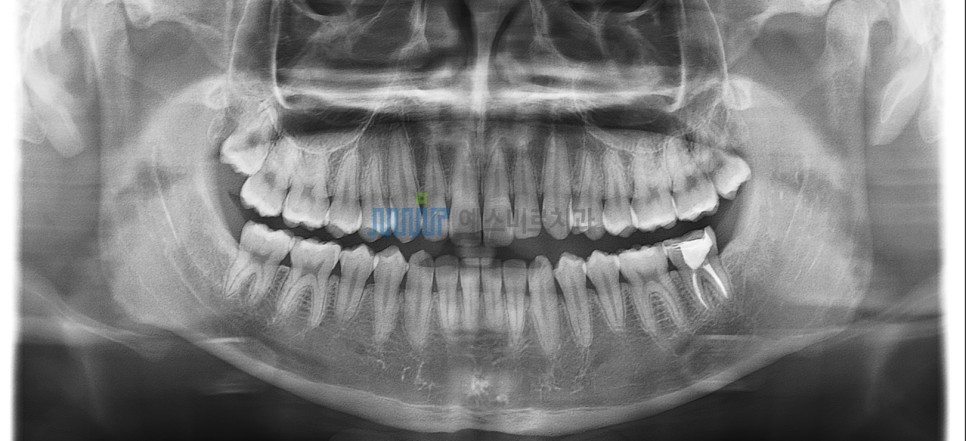

아래 사랑니 발치 전

사랑니 발치 후에도 턱뼈는 변하지 않아요

그렇다면 사랑니는 왜 빼야할까요?

구강 건강을 위해서 입니다

특히 매복 사랑니는

단순히 '빼는 것'이 아니라

주변 치조골과 신경을 보호하면서

안전하게 제거하는 과정이 중요합니다